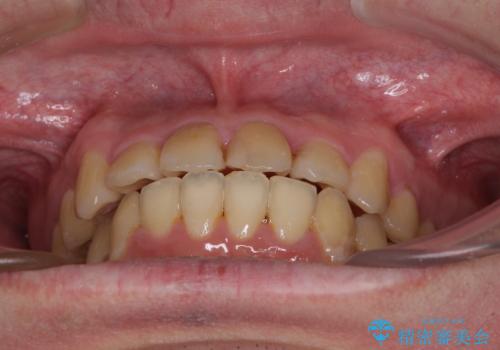

- 上下のデコボコと前歯のクロスバイトを改善したいとのことで来院された患者様です。

マウスピース矯正での自己管理には自信がないとのことで、ワイヤー装置による矯正治療を行うこととしました。

デコボコの程度は強かったのですが、口元の突出感はなかったため、非抜歯矯正としました。